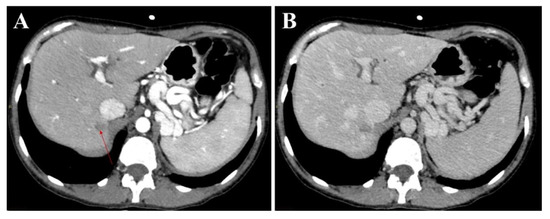

3.1. Atypical Liver Nodule Characteristics

3.2. Feasibility of Liver Biopsy

4. Discussion